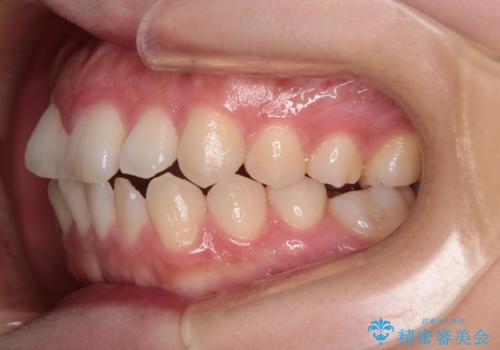

【インビザライン】前歯の凸凹を治したい

- 前歯の凸凹を主訴に来院されました。

インビザラインにて臼歯部の遠心移動を行いながら、できるだけ前歯が出ないように気を付けて治療を行っています。

遠心移動を行う必要があったので、患者様には顎間ゴムを使用していただきました。